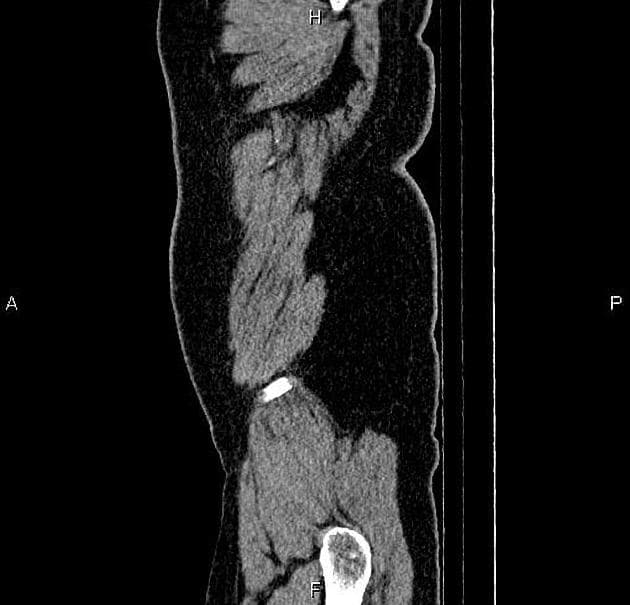

Đau đầu mới xuất hiện và liệt nửa người trái ở bệnh nhân đang điều trị ung thư phổi tế bào không nhỏ.

Phát hiện nhiều nốt (nodule) và khối (mass) ở vùng trên lều, trong đó tổn thương lớn nhất nằm ở thùy chẩm phải, kích thước khoảng 34 x 29 x 30 mm.

Các tổn thương ở nhu mô não (brain parenchyma), sọ vòm (calvarium) và màng não (meninges) vùng trán trái phù hợp với di căn nội sọ (intracranial metastases).

Di căn nội sọ (intracranial metastases)